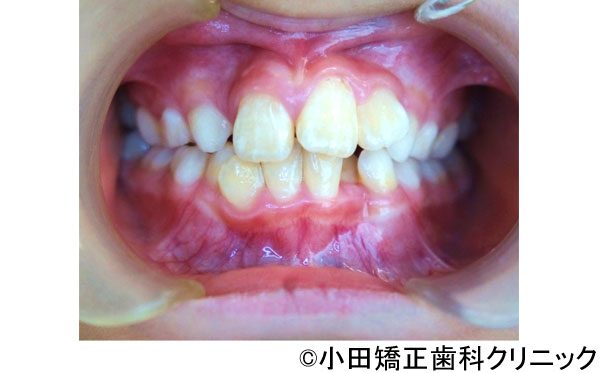

【症例3】呼吸から治して厳しいでこぼこ状態ではあるが、歯を抜くことなくしかも突出のない知的な口元に改善する治療

- 治療前

- 治療後

- 治療名

- 呼吸から治して厳しいでこぼこ状態ではあるが、歯を抜くことなくしかも突出のない知的な口元に改善する治療

- 患者様

- 9歳

- 費用

- 1,000,000円(税込)(永久歯治療を含む)

- 期間

- 早期治療2年+永久歯治療1年

治療内容

-

患者様の症状

厳しい上下歯列のでこぼこ不十分な鼻呼吸のため口呼吸が必要となり、舌、唇などの筋肉の良くない動き、つまり舌が、本来、飲み込むために上あごに引っ付くのではなく、下に下がり、口が開くことで頬が締まって上歯列は狭くなります。また下に下がった下の圧力で下歯列も内側に倒れて狭い舌歯列となります。

鼻呼吸不十分による口呼吸がもたらす締まりにかけるやや突出した口元、不適切な姿勢、免疫機構の不善によりもたらされる過大な感染症のリスク -

治療法

上歯列に固定式の拡大装置により左右の上あごの接合部を拡げて鼻呼吸に改善する。舌が収まる空間を得るために下歯列にも特殊な拡大装置により歯を支える骨の付け根からしっかりと広げる。

治療結果

美しい口元、顔立ち、健康的な呼吸をもたらし、鼻呼吸を導く徹底した従来より効果の大きい広げる装置により、厳しいでこぼこ状態を歯を抜くことなく、しかも突出の全くないきれいな口元に改善しました。